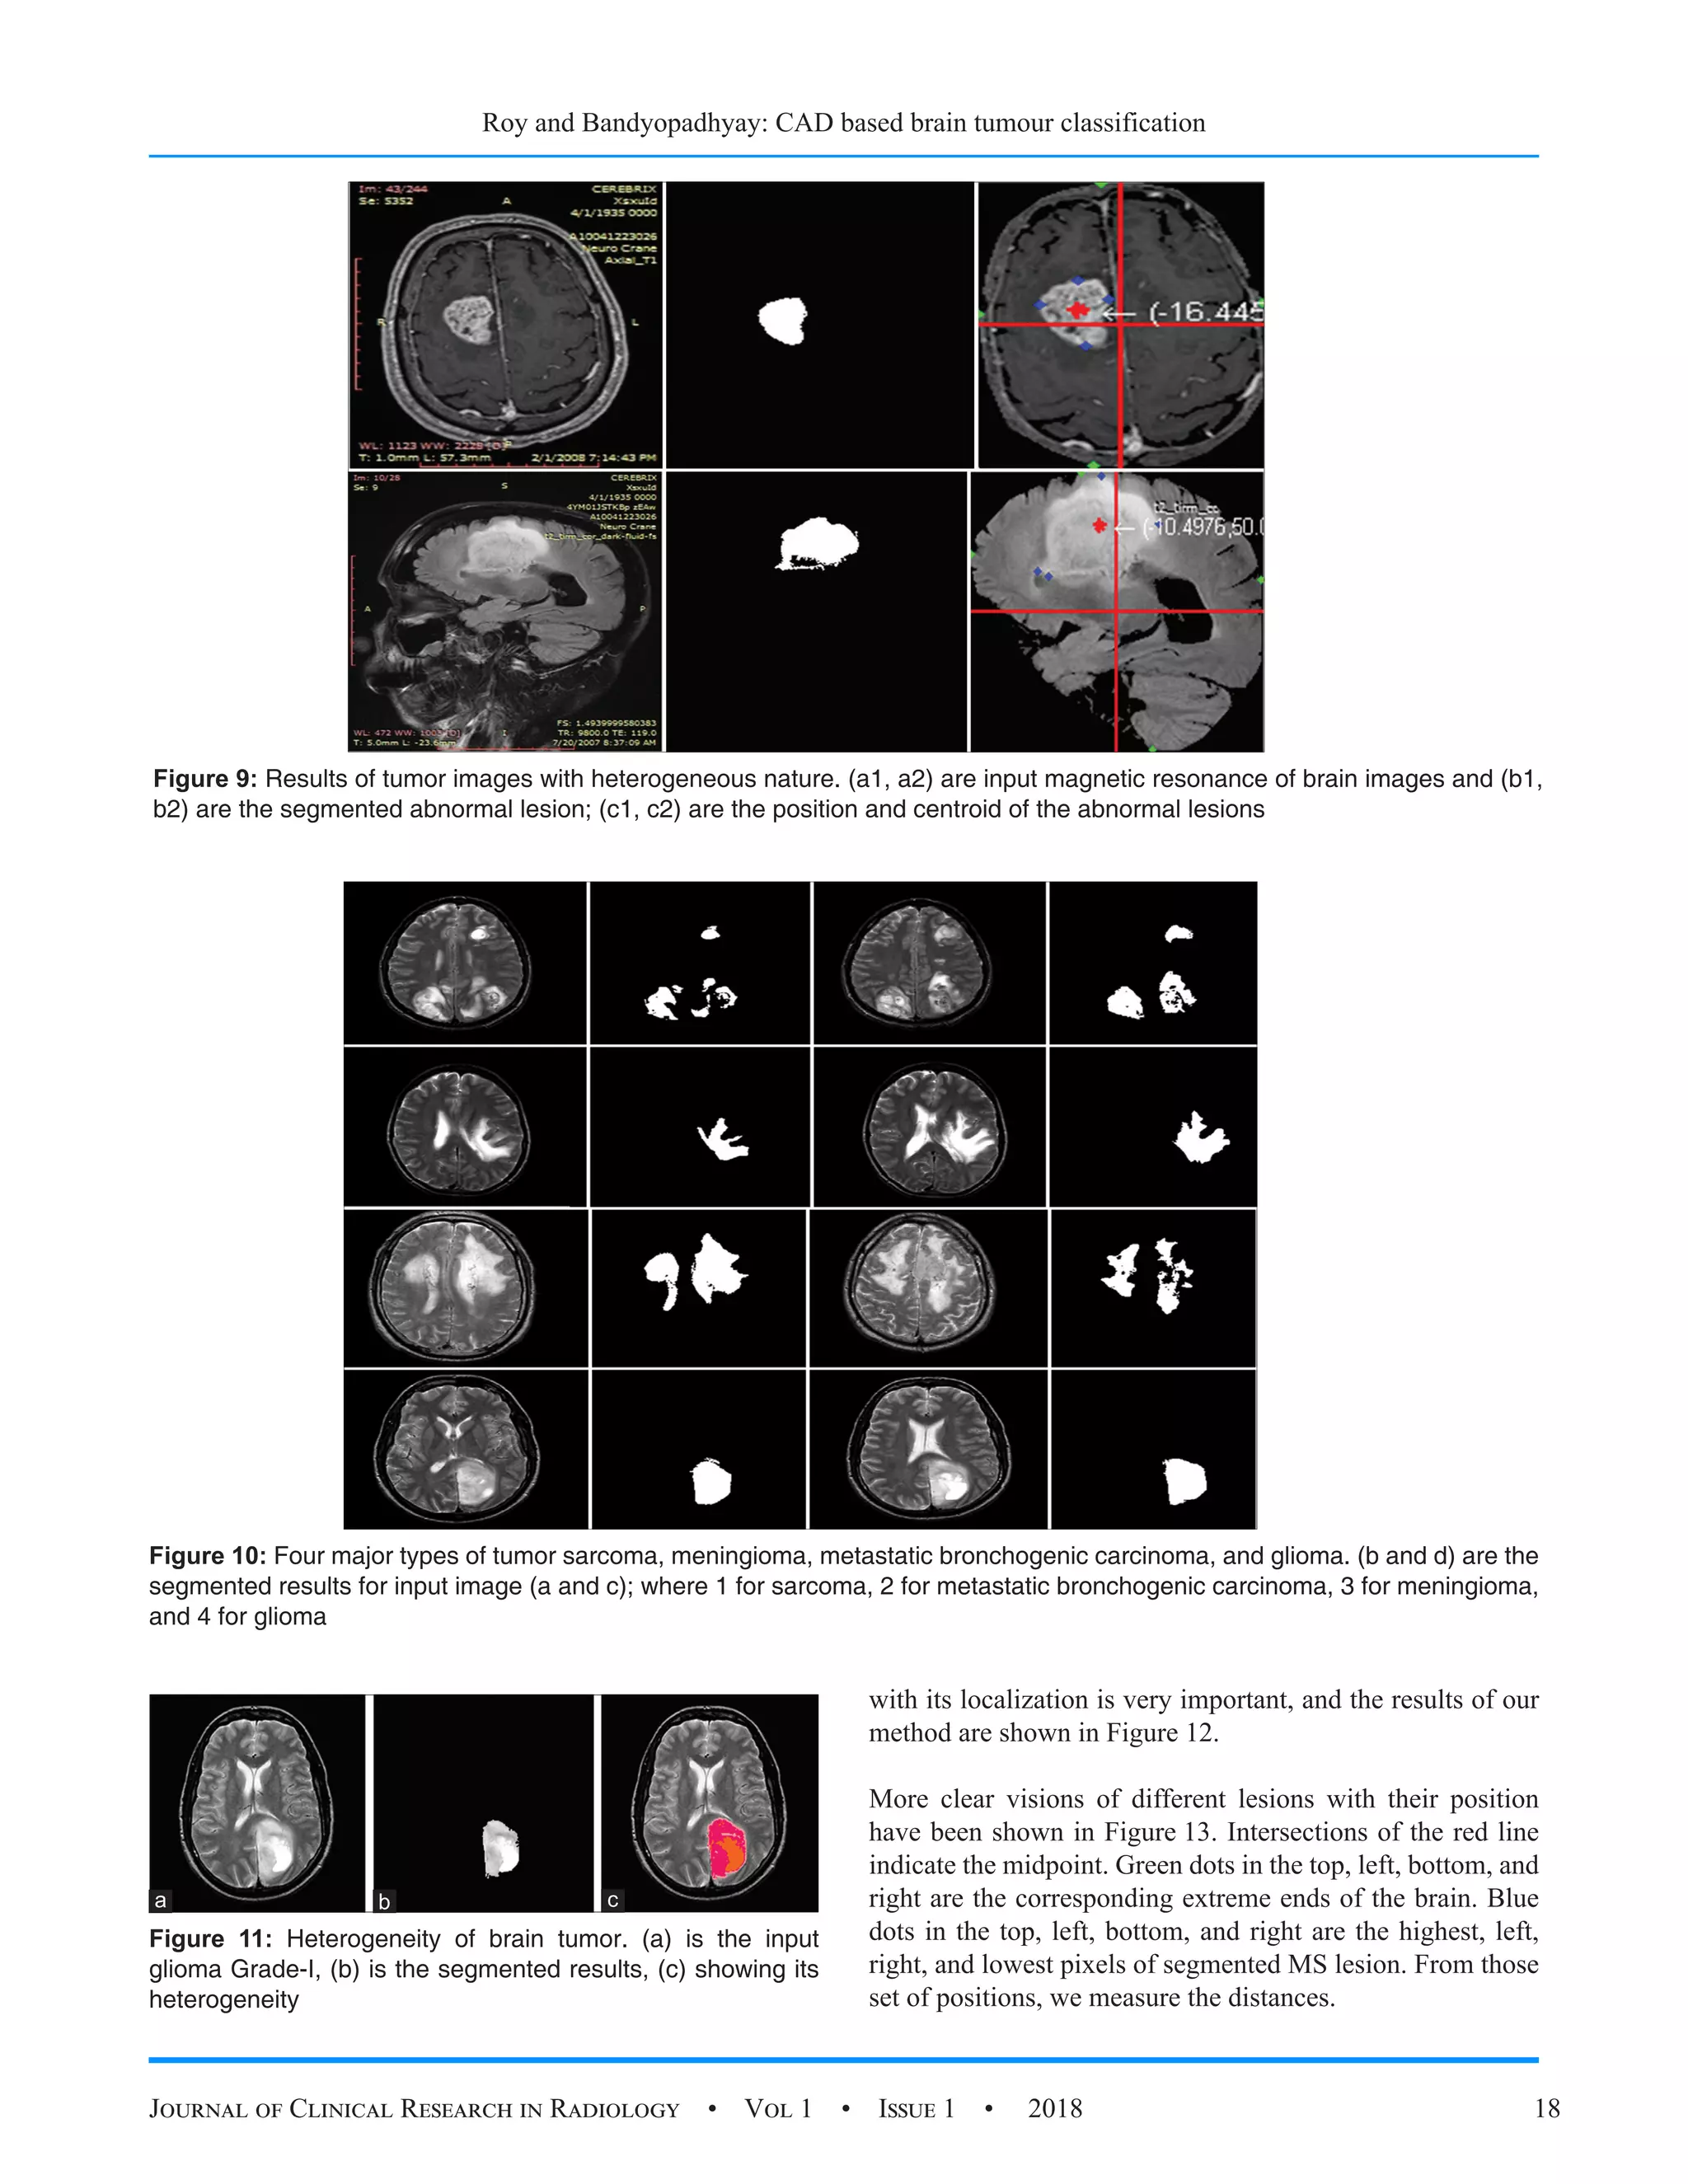

Figure 9: Results of tumor images with heterogeneous nature. (a1, a2) are input magnetic resonance of brain images and (b1,

b2) are the segmented abnormal lesion; (c1, c2) are the position and centroid of the abnormal lesions

Figure 10: Four major types of tumor sarcoma, meningioma, metastatic bronchogenic carcinoma, and glioma. (b and d) are the

segmented results for input image (a and c); where 1 for sarcoma, 2 for metastatic bronchogenic carcinoma, 3 for meningioma,

and 4 for glioma

Segmentation results of four major types of tumor sarcoma,

meningioma, metastatic bronchogenic carcinoma, and glioma

have been shown in Figure 10. The problem of multiple

false detection has been solved using proposed segmentation.

From the segmented results it clearly shows that proposed

method can segment different types of the tumor with reduced

error with high accuracy visually.